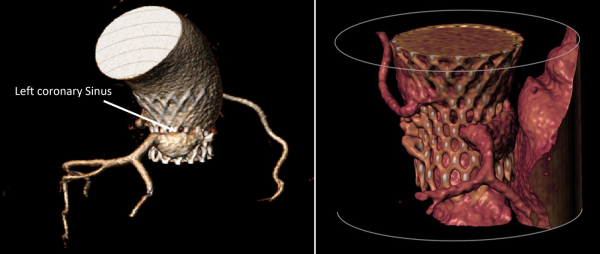

Figure 3 : séquestration du sinus coronaire gauche

Figure 4

Figure 5

Figure 6

Figure 7 : Longueur du feuillet de la cusp aortique > hauteur de la JST

Simulation de l’implantation de l’Evolut 29

Figure 8 : gauche : Valve – Sinus < 2mm - droite : Valve – Coronaire > 4 mm